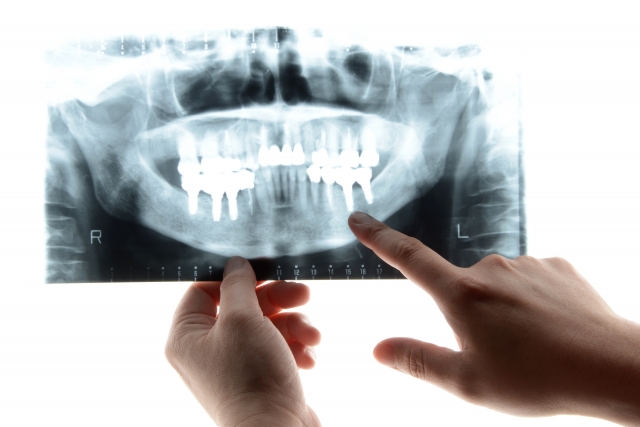

インプラント治療についての基礎知...